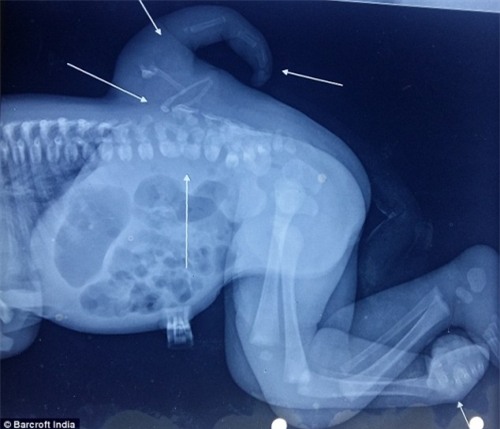

Bé gái người Ấn Độ Varsha Sena được sinh ra tại bệnh viện Rao Hindu Bara ở bang Delhi, Ấn Độ. Điều đặc biệt là trên lưng của bé có xuất hiện thêm một chân thừa, mặc dù bé vẫn có hai chân như bình thường và các chức năng cơ thể vẫn ổn định.

Các bác sĩ cho biết, bé Varsha mắc một chứng bệnh khá hiểm gặp gọi là polymelia. Dị tật bẩm sinh này khiến trẻ em sinh ra với chi thừa, thường là cánh tay hoặc cánh chân. Theo đó, chứng bệnh polymelia này thường chỉ phát triển trong quá trình phôi thai.

“Nguyên nhân có thể do phôi thai phát triển thành cặp song sinh dính liền nhau nhưng một trong hai thai nhi ngừng phát triển, để lại những phần thừa, thường là các chi trên cơ thể của em bé còn lại”, bác sĩ Daljit Singh, người điều hành ca mổ cho biết.